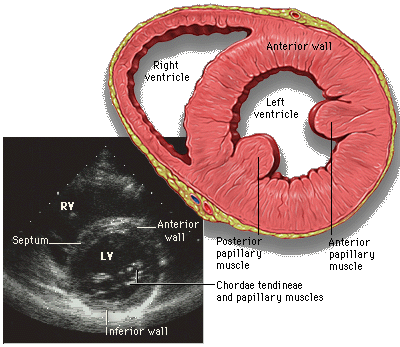

• Cardiac Echocardiography: Basics and Uses

• Anatomy and Physiology of the Heart